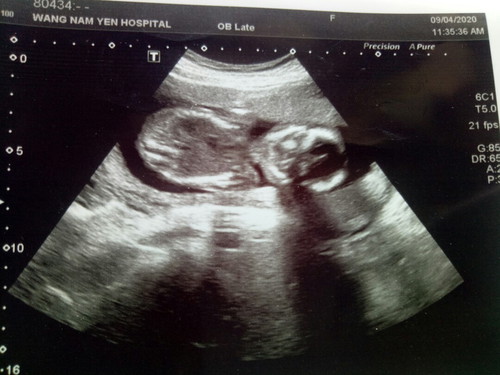

วันนี้หมอซาวด์ให้แล้วค่ะ

ใครดูออกบอกทีค่ะชายหรือหญิง หมอบอกว่า10กันยาค่ะกำหนดคลอดขอเสียงคนคลอดเดือนกันยาหน่อยจ้า

นี้ภาพตัวน้องค่ะ ไม่เห็นเพศ คราวหน้าถ้าหมอไม่บอกถามหมอนะคะ

ไม่เห็นช่วงอวัยวะเพศเลยค่ะ รออายุครรภ์มากกว่านี้หน่อยนะคะ